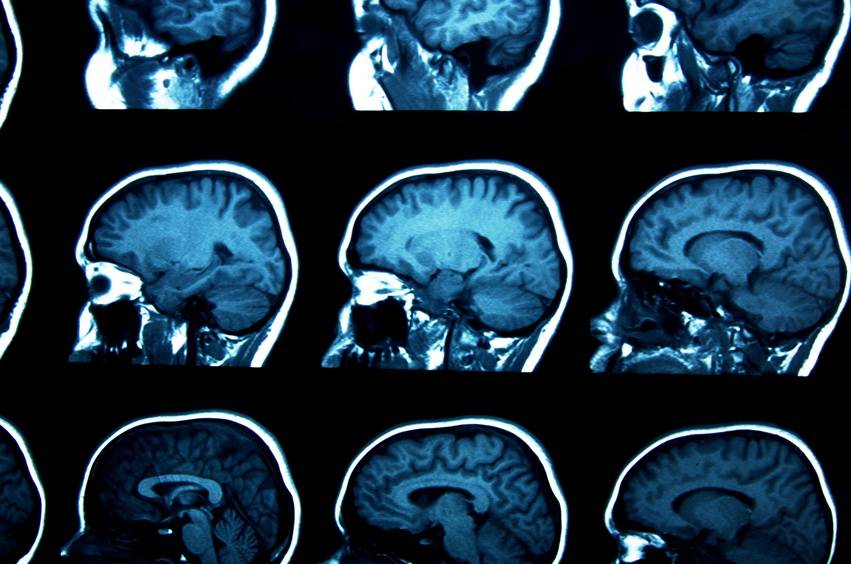

The PsychENCODE consortium, established in 2015 and dedicated to illuminating the molecular mechanisms underlying schizophrenia, bipolar disorder, and autism spectrum disorder, presents findings based on the examination of human brains at the cellular level. The studies are published today in the journals Science, Science Translational Medicine and Science Advances.

The set of studies presented here constitutes a valuable and important resource for facilitating the identification of regions and mechanisms of the genome that regulate gene expression according to cell types and stages of brain development that may be related to mental illnesses of unknown nature, such as autism or schizophrenia.The genetic expression in the prefrontal cortex, a region of the brain involved in complex mental tasks, such as reasoning or social behavior, which could be related to mental illness, receives special treatment in one of the works.

As a whole, the published works gather information from thousands of samples and different ages and ethnicities, addressing the difficulty of linking common genetic variations with the susceptibility or risk of developing certain mental illnesses.The results gain systemic value by being part of the PsychENCODE consortium, which, in its nearly 15 years of existence, aims to generate a multiplicity of data on the genetic regulation of the human brain.